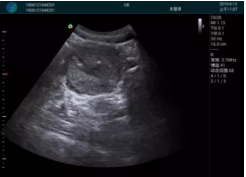

可視化穿刺引導(dǎo)

M20實(shí)時引導(dǎo):向包塊后方間隙注射利多卡因

清晰顯示腺體內(nèi)低回聲快影,邊界清晰,包膜較光滑

確定進(jìn)針路徑并實(shí)時監(jiān)測抽吸針與腫塊位置關(guān)系

抽吸針進(jìn)入腫塊內(nèi)部進(jìn)行旋切

抽吸過程中可見腫塊明顯縮小,并根據(jù)腫塊位置改變針道位置

抽吸旋切后再進(jìn)行超聲復(fù)查,原腫塊區(qū)域未見殘留組織及出血

超聲引導(dǎo)下抽吸旋切取出的腫塊組織